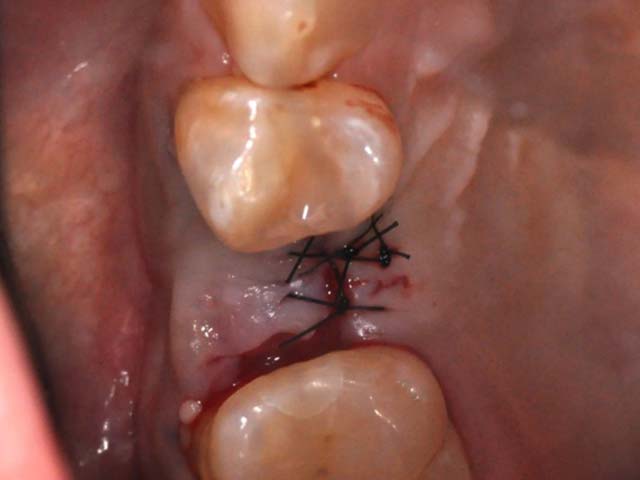

齒槽骨保存術+植牙 首頁 案例分享 人工植牙 齒槽骨保存術+植牙 STEP1拔除掉無法使用的斷裂牙根 STEP2齒槽骨保存術—使用骨粉填補拔牙傷口 術前 V.S 術後 植牙第一階段—植入牙根 植牙第二階段—製作正式假牙